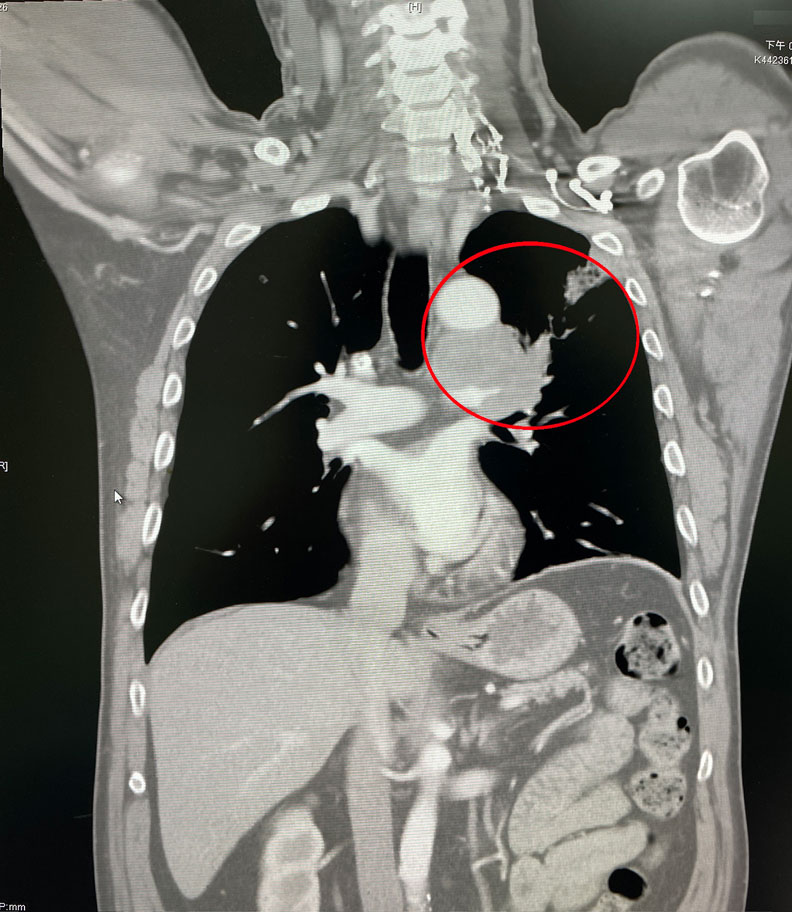

彰化一名57歲的陳先生從事庭園造景工作,菸齡30年,菸癮最大時一天可以抽到三包菸,起初有喘不停、完全沒有聲音的症狀,於別家醫院接受氣喘治療兩年多,都沒有太大的改善,沒想到卻意外被宣判小細胞肺癌末期,左上肺的腫瘤合併多處淋巴腺轉移,僅剩四個月的生命,輾轉下接受烏日林新醫院胸腔內科許人文醫師,為他量身打造的抗癌治療,竟成功扭轉命運!

除此之外,也趁勝追擊一步一步地把癌細胞縮小,安排正子電腦斷層掃描,竟然發現先前在左上肺和轉移到縱膈腔、頸部淋巴腺一大片的癌細胞,都已經完全消失不見了,僅需1年半治療小細胞肺癌,成功把癌細胞全部殺死。